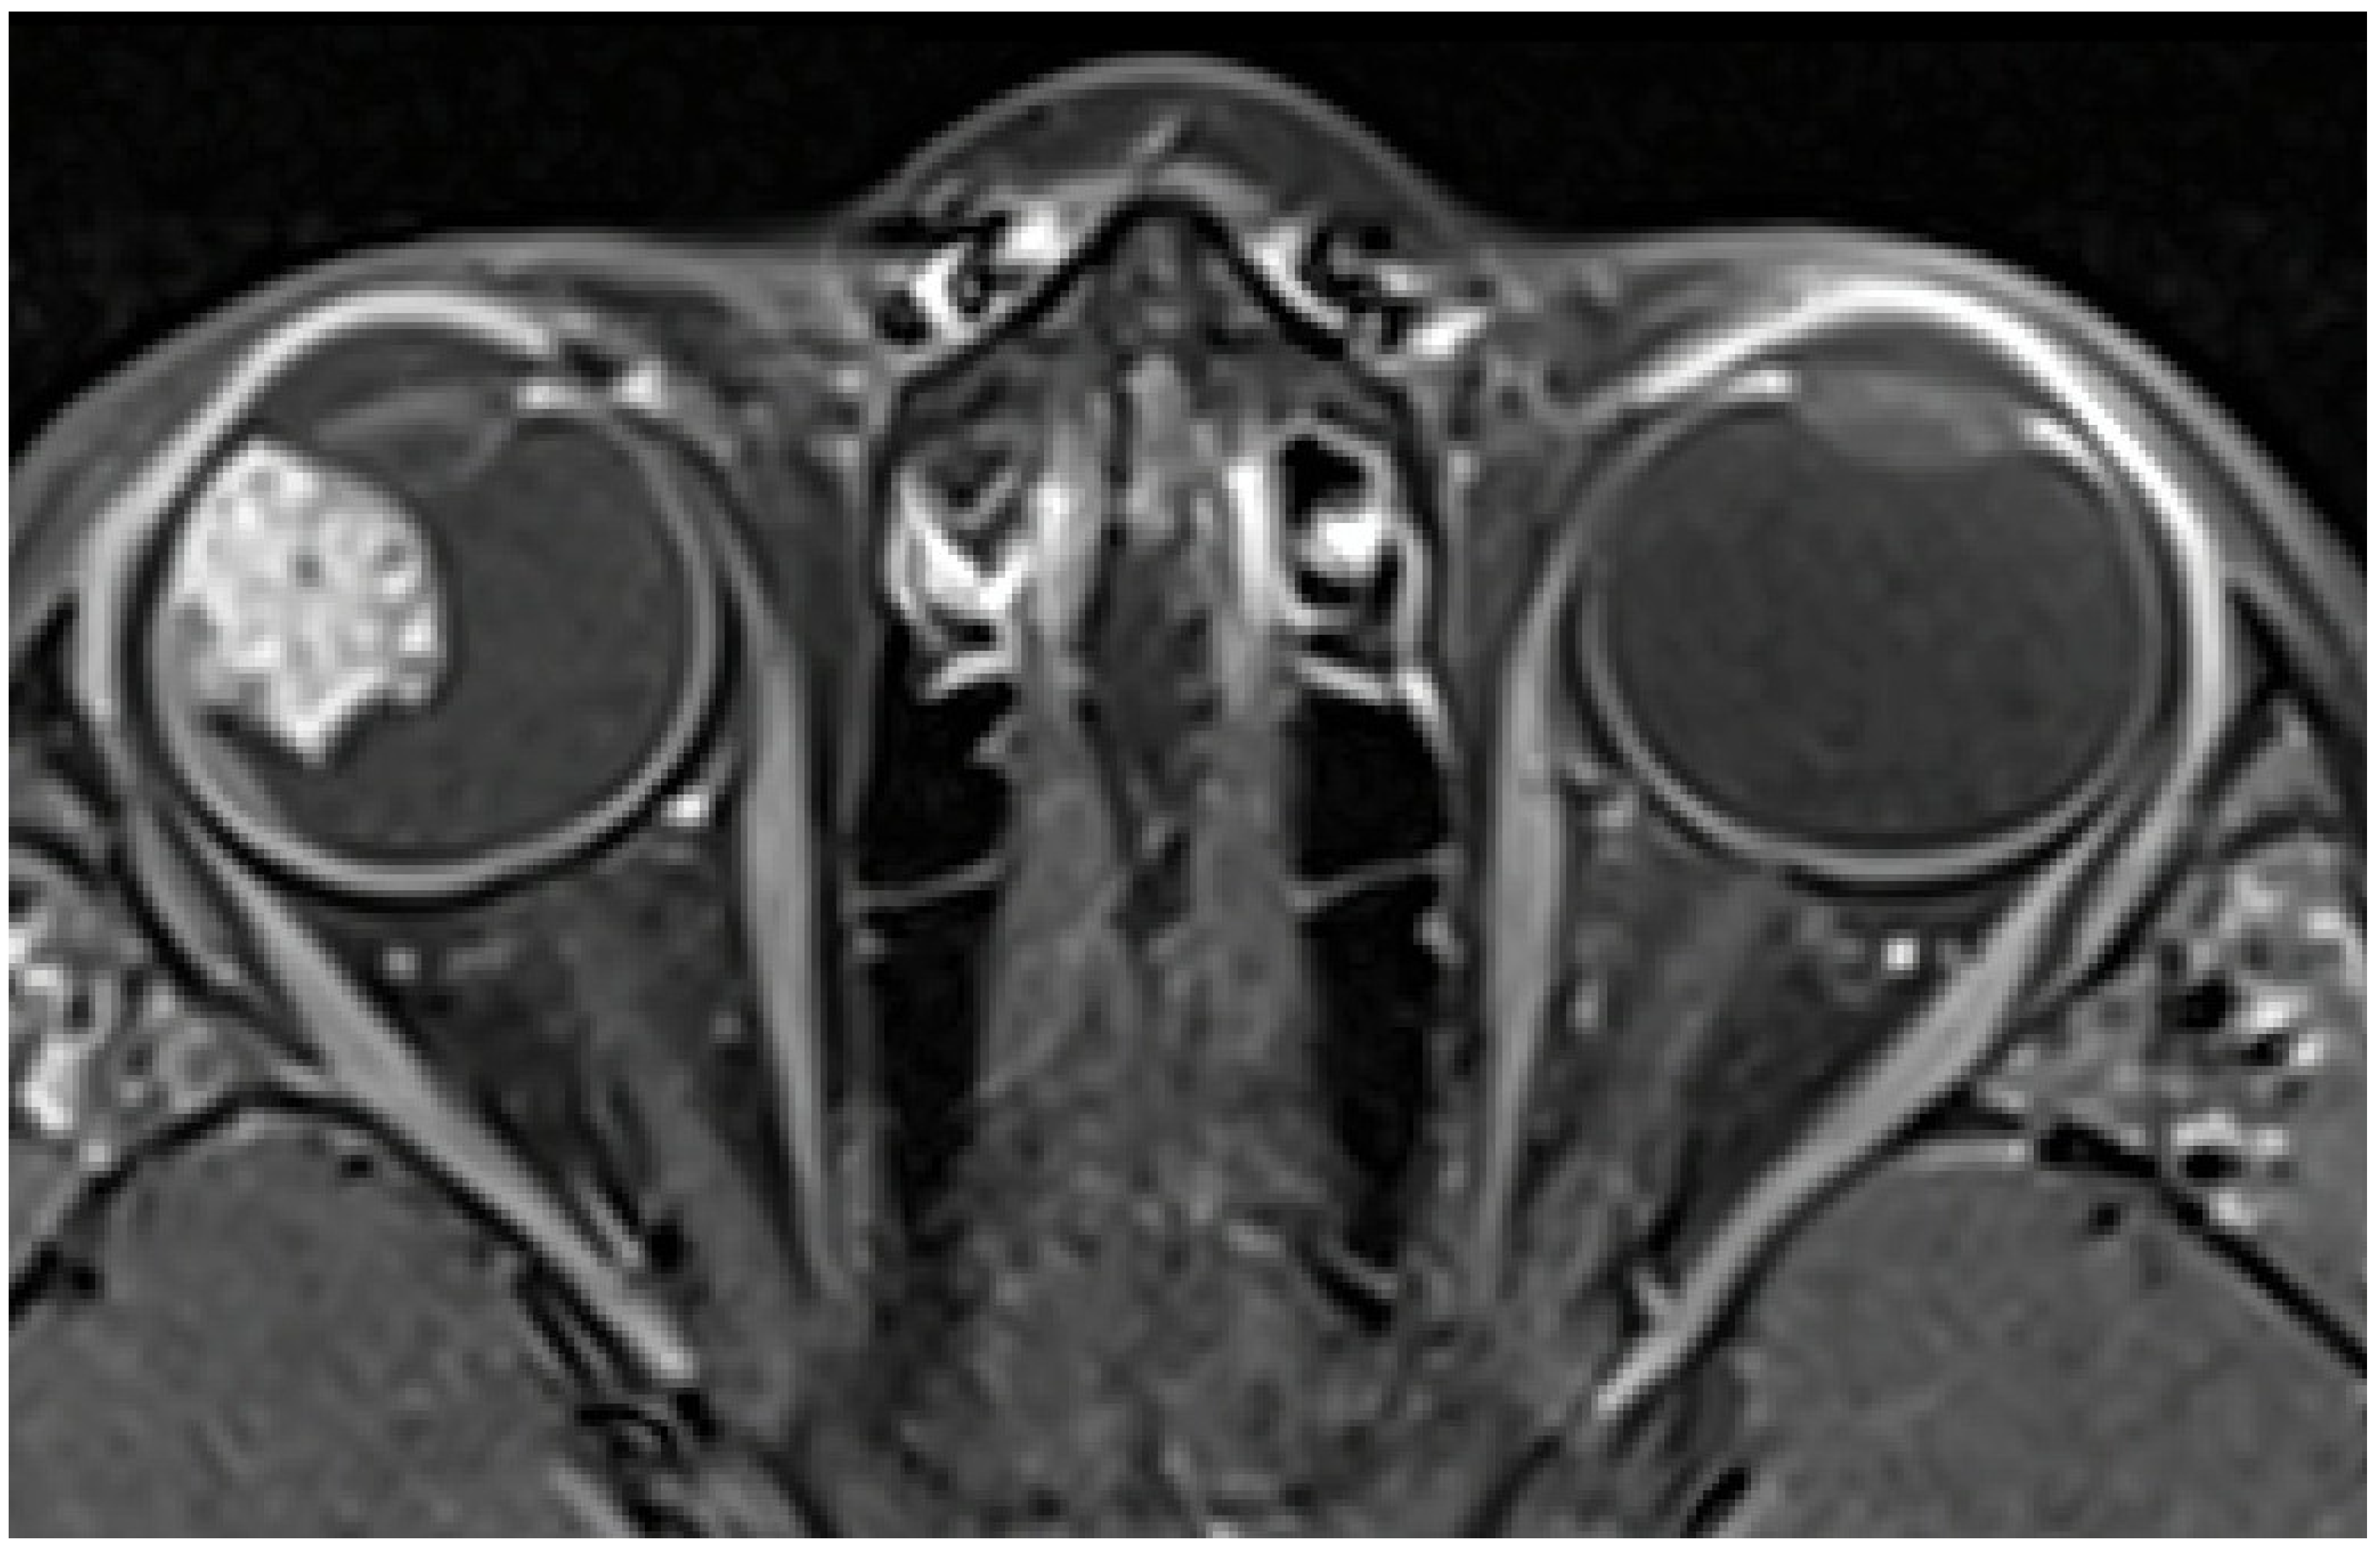

Magnetic Resonance Imaging (MRI) showed an irregular-surfaced ciliary body mass of heterogenic intensity, size of 13 × 11 × 14 mm (Figure 2) in the antero-lateral part of the right eye, with a heterogenous enhancement pattern. No scleral or extrabulbar invasion was revealed. Comprehensive additional examinations, including abdomen ultrasonography, chest radiograph, and blood analyses, revealed no additional abnormalities.

Figure 2. MRI showing a ciliary body mass with heterogenic intensity in the right eye.